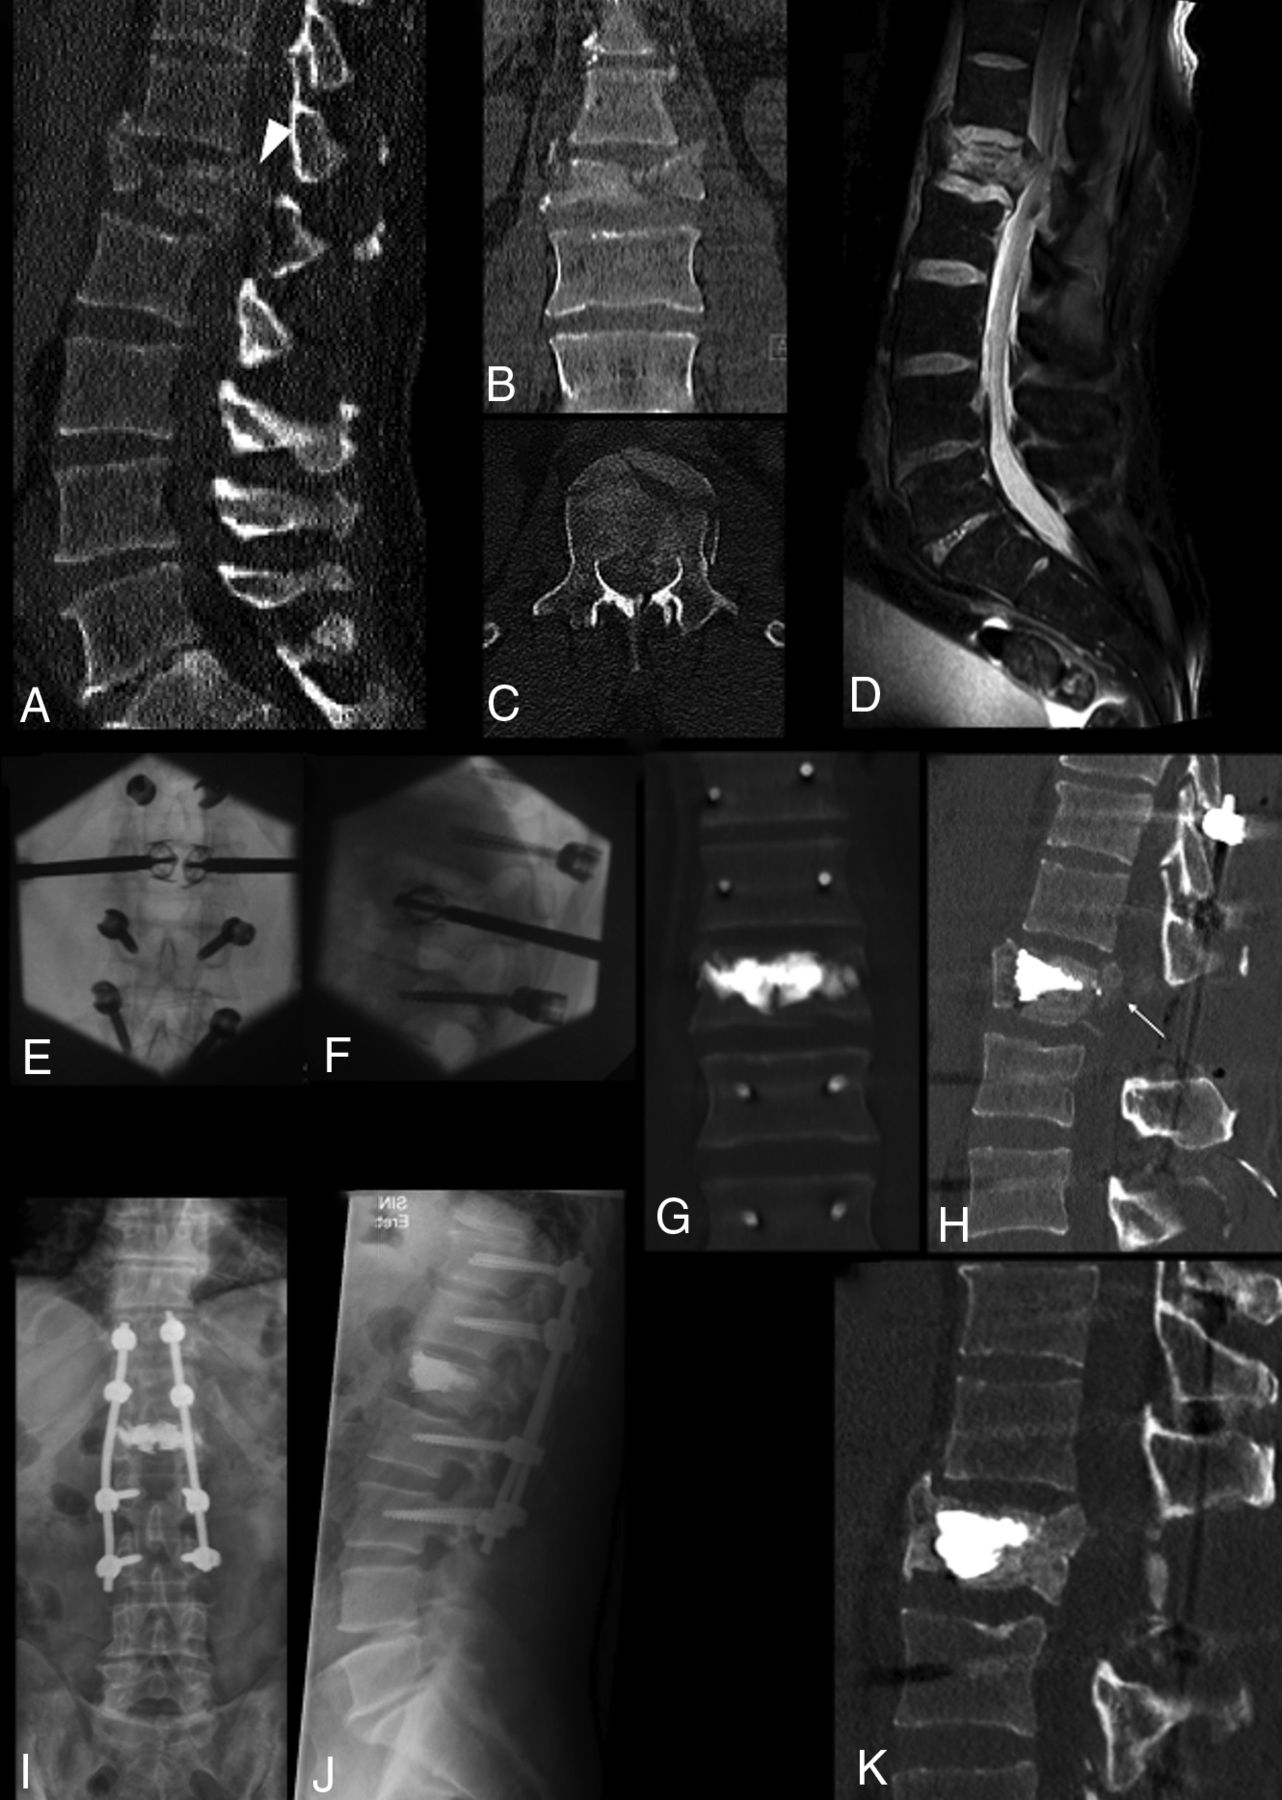

Complete burst fracture of L1 following high-energy trauma in a 40-year-old man with marked vertebral body fragmentation (A–C) and posterior wall retropulsion (arrowhead, A). Sagittal fat-saturated proton density MR image (D) shows an epidural hematoma and compression of the conus medullaris, but the patient was neurologically intact. The patient underwent surgical treatment in a hybrid operation room, including, in sequence, L1 decompressive laminectomy, pedicular screw placement, fracture reduction and vertebral body augmentation with percutaneous bilateral SpineJack, and posterior stabilization with spinal rods (E and F). Postprocedural CT (G and H) shows fracture and kyphosis reduction and, most important, central canal clearance (arrow, H) through ligamentotaxis. Notably, no maneuvers of direct fragment impaction or of posterior fracture distraction were performed. Follow-up imaging with standing plain films at 6 months (I and J) and with CT at 12 months (K) shows preserved vertebral body height and alignment and osseous healing around the cement cast. In this case, a more invasive procedure of corpectomy and anterior column stabilization could be successfully avoided by armed kyphoplasty.

In this study, AKP using recently introduced vertebral body fracture internal distraction devices such as VBS and SJ was safely able to obtain VBH restoration and PWR correction in traumatic (Figs 3 and 4), osteoporotic (Figs 1 and 3), and neoplastic burst fractures (Fig 2). It was used as a stand-alone minimally invasive procedure in most cases or in combination with a posterior surgical approach (Fig 4), but without the need to perform any direct form of PWR correction. This minimally invasive approach had only 2 periprocedural complications, both with benign clinical resolution; showed durable results at follow-up; and required no re-intervention on the target level.

AKP was performed using VBS in 46 levels, and SJ, in the remaining 7. We tend to use SJ for AKP when bone mass is preserved, especially in young patients with traumatic mechanism of fracture and impacted morphology of the fracture, to the impacted morphology needs a powerful internal fracture distraction, while we rather use VBS in bone of poor quality with a high degree of vertebral body fragmentation, osteoporosis, and lytic lesions, in which the vertebral body rather needs an internal scaffold to restore its stability and axial-load capability.38